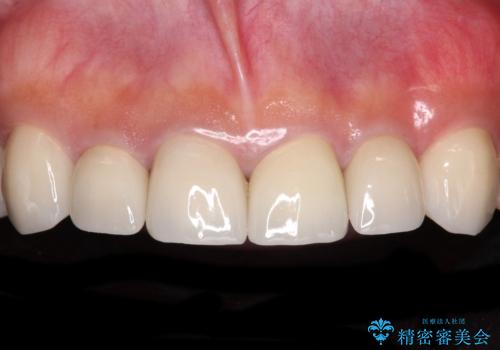

【モニター】インビザラインで口を閉じやすく

- 前に出ている上顎前歯が気になるとのことで来院された患者様です。

インビザラインを用い、IPR(歯と歯の間を削る)と歯列全体を後方に移動させることで、可能な限り前歯の突出感を改善することとしました。

元々の歯列も整っており、横顔の印象の出っ歯ではなかったため、仕上がりに満足できない可能性があると心配しておりましたが、口が閉じやすくなり、患者様には大変満足していただきました。